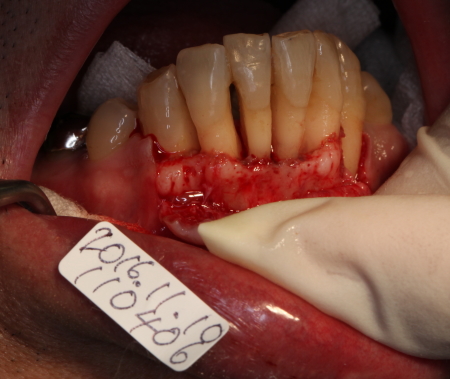

FOP

2016-11-10